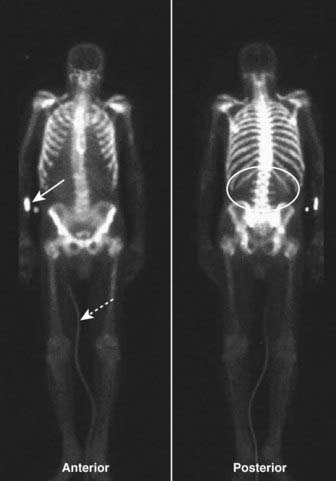

image Unlike the convention used for viewing other studies in radiology, the patient’s right side is not always on your left in nuclear scans. This can be confusing, so make sure you look for the labels on the scan (Fig. 1).

image

Figure 1 Normal bone scan.

Anterior and posterior views are frequently obtained, since each view brings different structures closer to the gamma camera for optimum imaging, e.g., the sternum on the anterior view (solid white arrow) and the spine on the posterior view (dotted white arrow). Notice that the kidneys are normally visible on the posterior view (white oval). Unlike the convention used in viewing other studies in radiology, the patient’s right side is not always on your left. On posterior views, the patient’s right side is on your right. This can be confusing, so make sure you look for the labels on the scan. In many cases a white marker dot will be located on the patient’s right side (white circles).